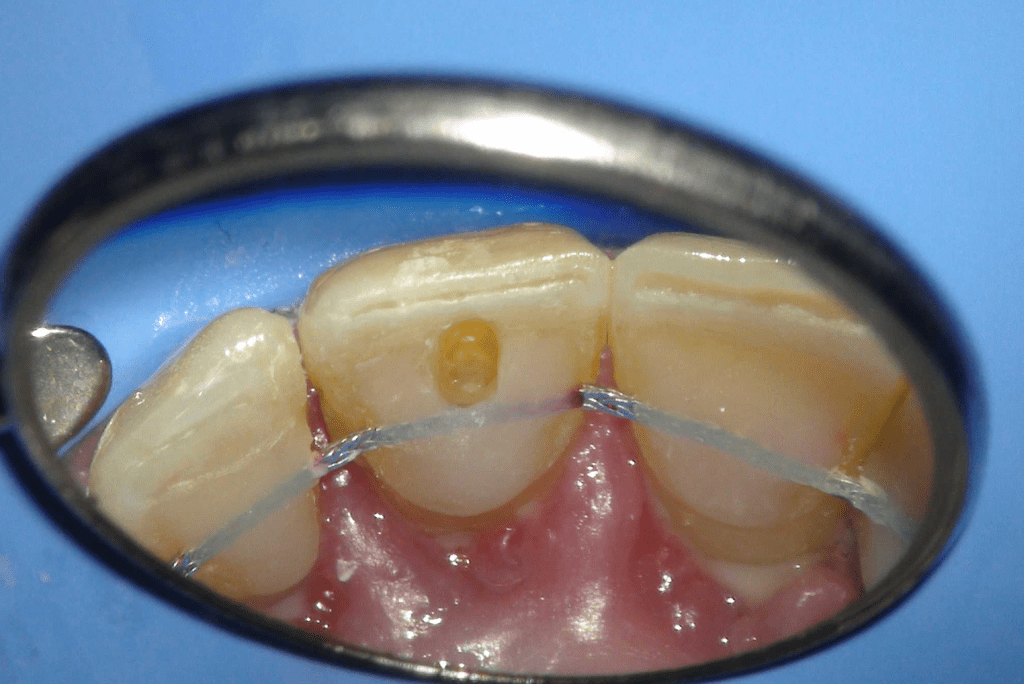

Pulpotomía biodentine + reco preendio